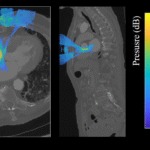

With prolonged aging, medicine is facing considerable challenges. In this fight against diseases, creating new imaging and therapy tools is essential for an increased understanding of pathologies and an improved patient care. Our institute Physics for Medicine Paris, also known as Institut Physique pour la Médecine, is a French research unit (Inserm/ESPCI Paris-PSL/CNRS) gathering physicists experts in ultrasound waves. We invent innovative technologies for medical imaging and therapy, which translate to three main field of medicine: cancer, cardiovascular diseases and neurosciences.